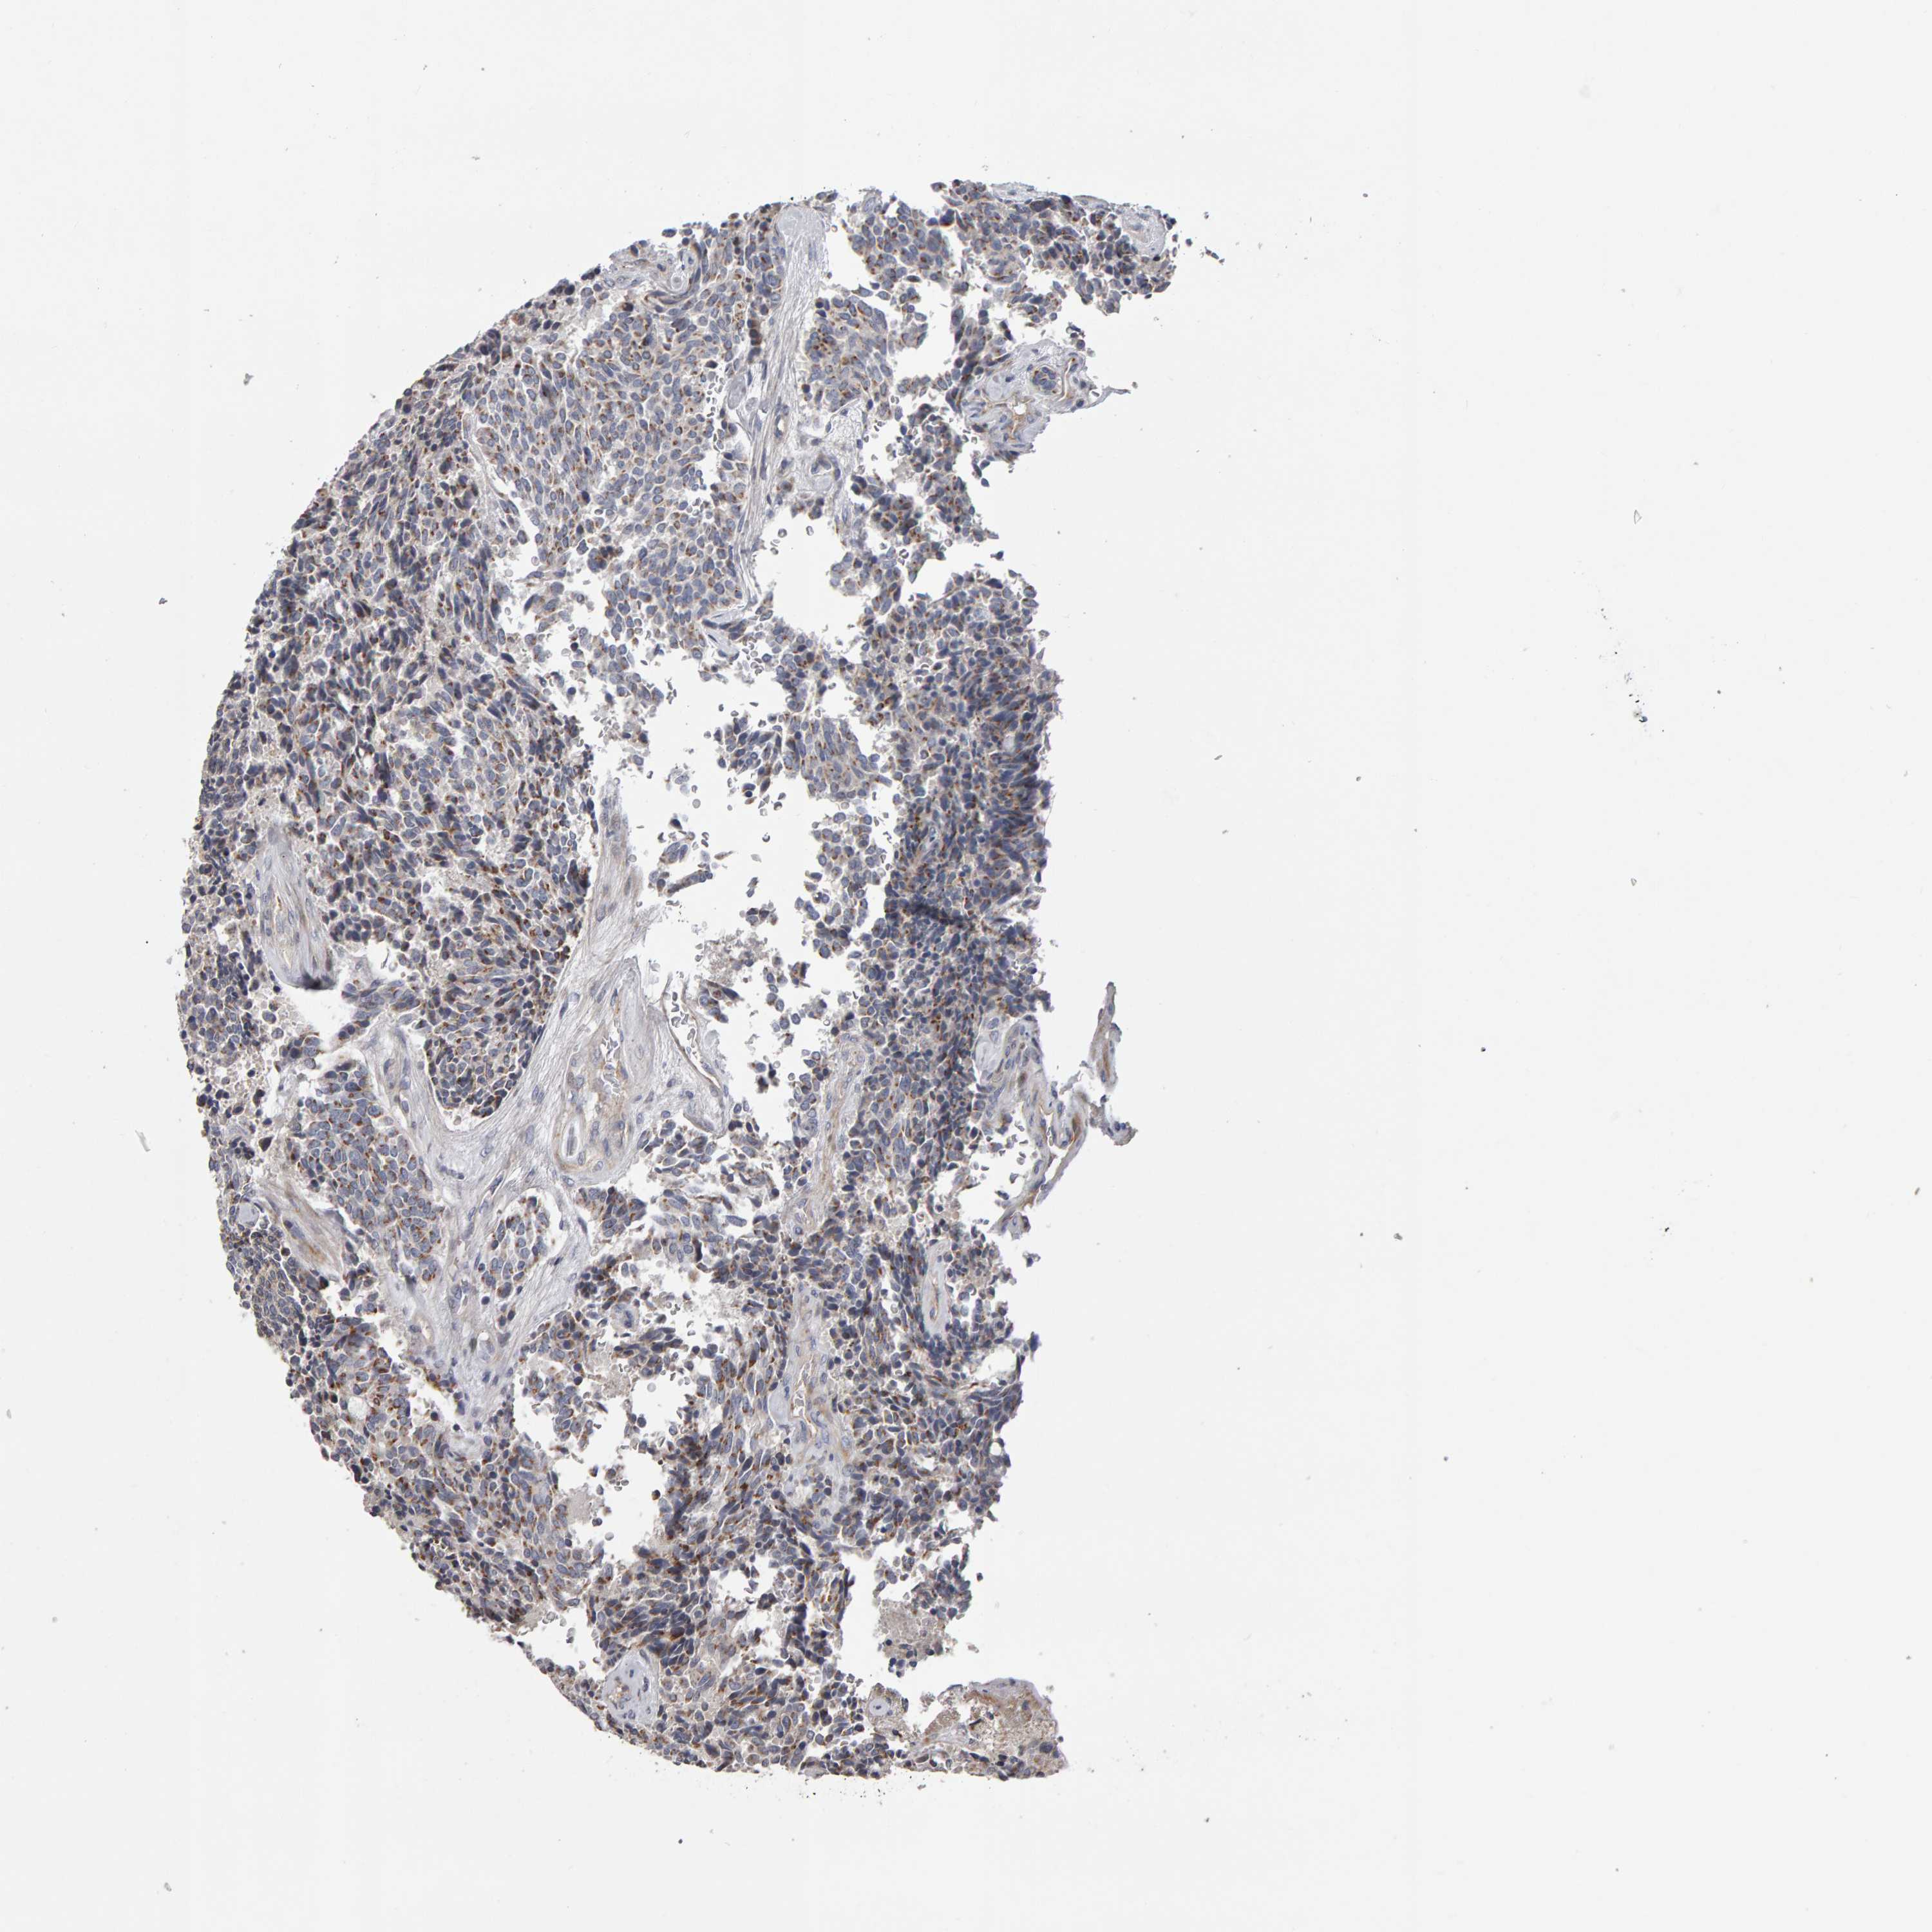

CANT1